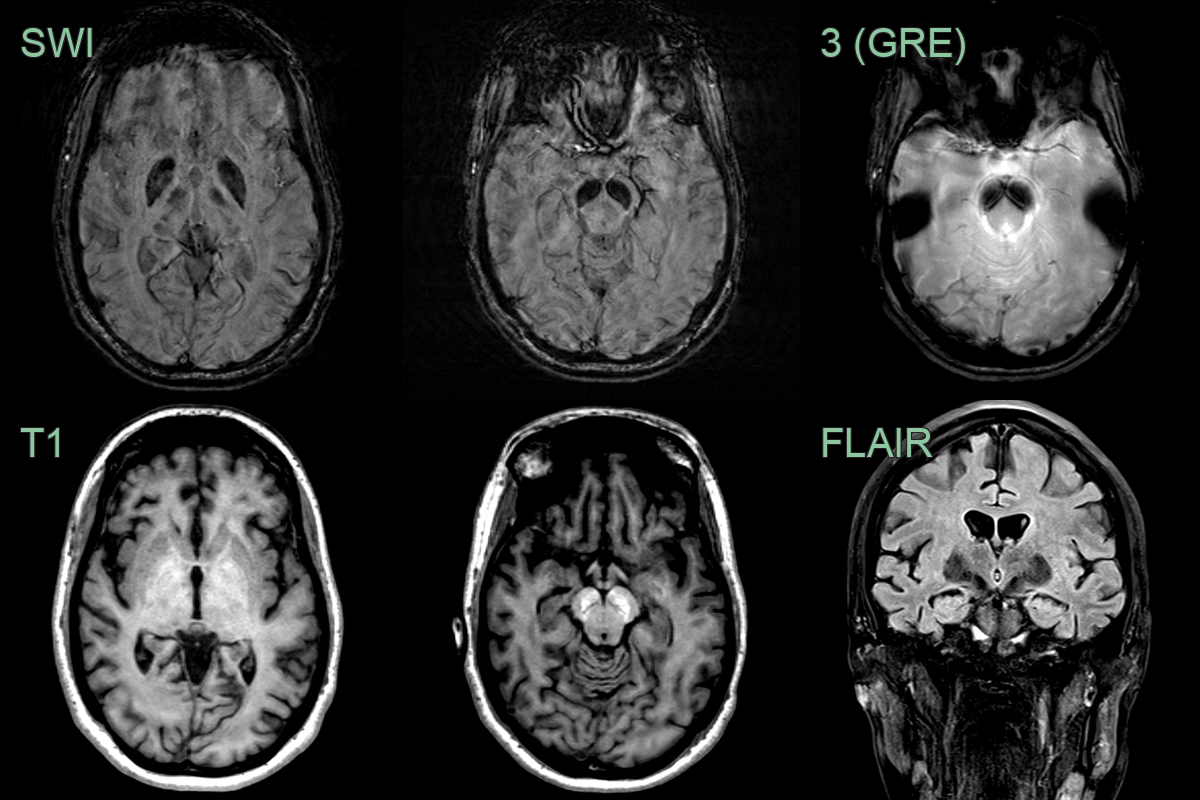

• A 25-year-old patient presented with possible seizures and parkinsonism.

• MRI showed pronounced iron deposition in the globi pallidi and substantia nigra.

• The substantia nigra T1-hyperintensity was typical for the diagnosis of BPAN.